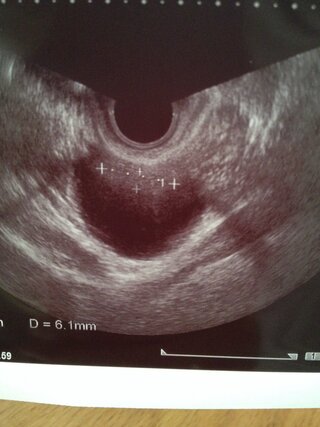

卵巣の腫れが5cmと言われ二週間後に再度受診する予定です このエコーで 卵 Yahoo 知恵袋

卵巣が4センチほど腫れており中に液体があります 膣内エコーで見てる時 Yahoo 知恵袋